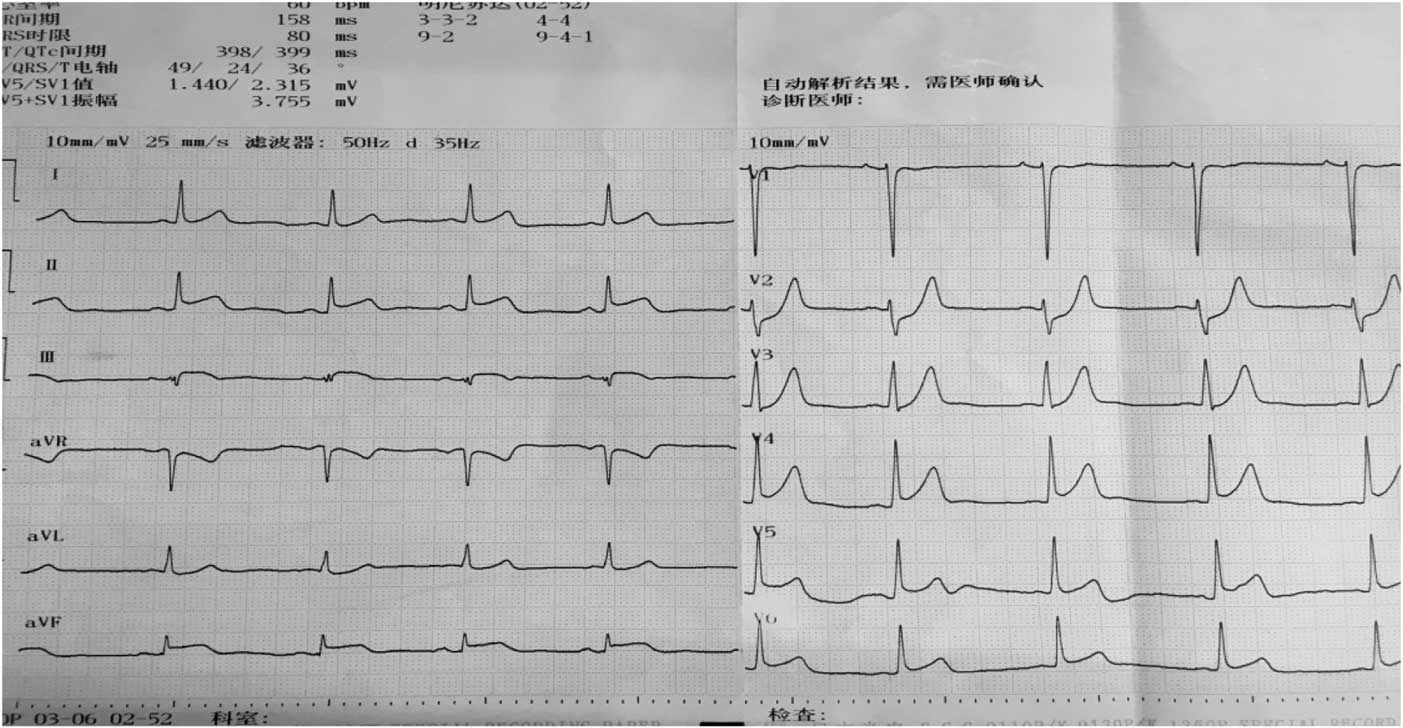

A 22-year-old male patient with a past medical history of nephrotic syndrome due to membranous nephropathy, which was diagnosed by renal biopsy 1 year ago, was admitted to the emergency room and transferred to our cardiac care unit with the complaint of chest pain along with dizziness, headache, and radiating pain to his left arm for 4 hours. The patient took no drugs in the past 6 months. On clinical examination, his pain was reported to be 5/10 according to the visual analogue pain scale, he was afebrile, with a maximum temperature of 36.6°C, and had ortho-arteriotony, with a blood pressure of 128/85 mmHg, and no tachycardia or bradycardia (pulse rate of 66 beats per minute). The patient’s face was bloated, but there was no jugular venous distention, muffled breath sounds, rhonchi or moist rale, the third or fourth heart sound gallop, pericardial rub, peritoneal irritation, hepatosplenomegaly, or leg oedema. Electrocardiogram on admission showed that ST elevated to 0.1–0.2 mv in II, III, aVF, and V4–V6 (Fig 1).

Figure 1 Electrocardiogram on admission shows elevated 0.1–0.2 mv in II, III, aVF, and V4–V6.